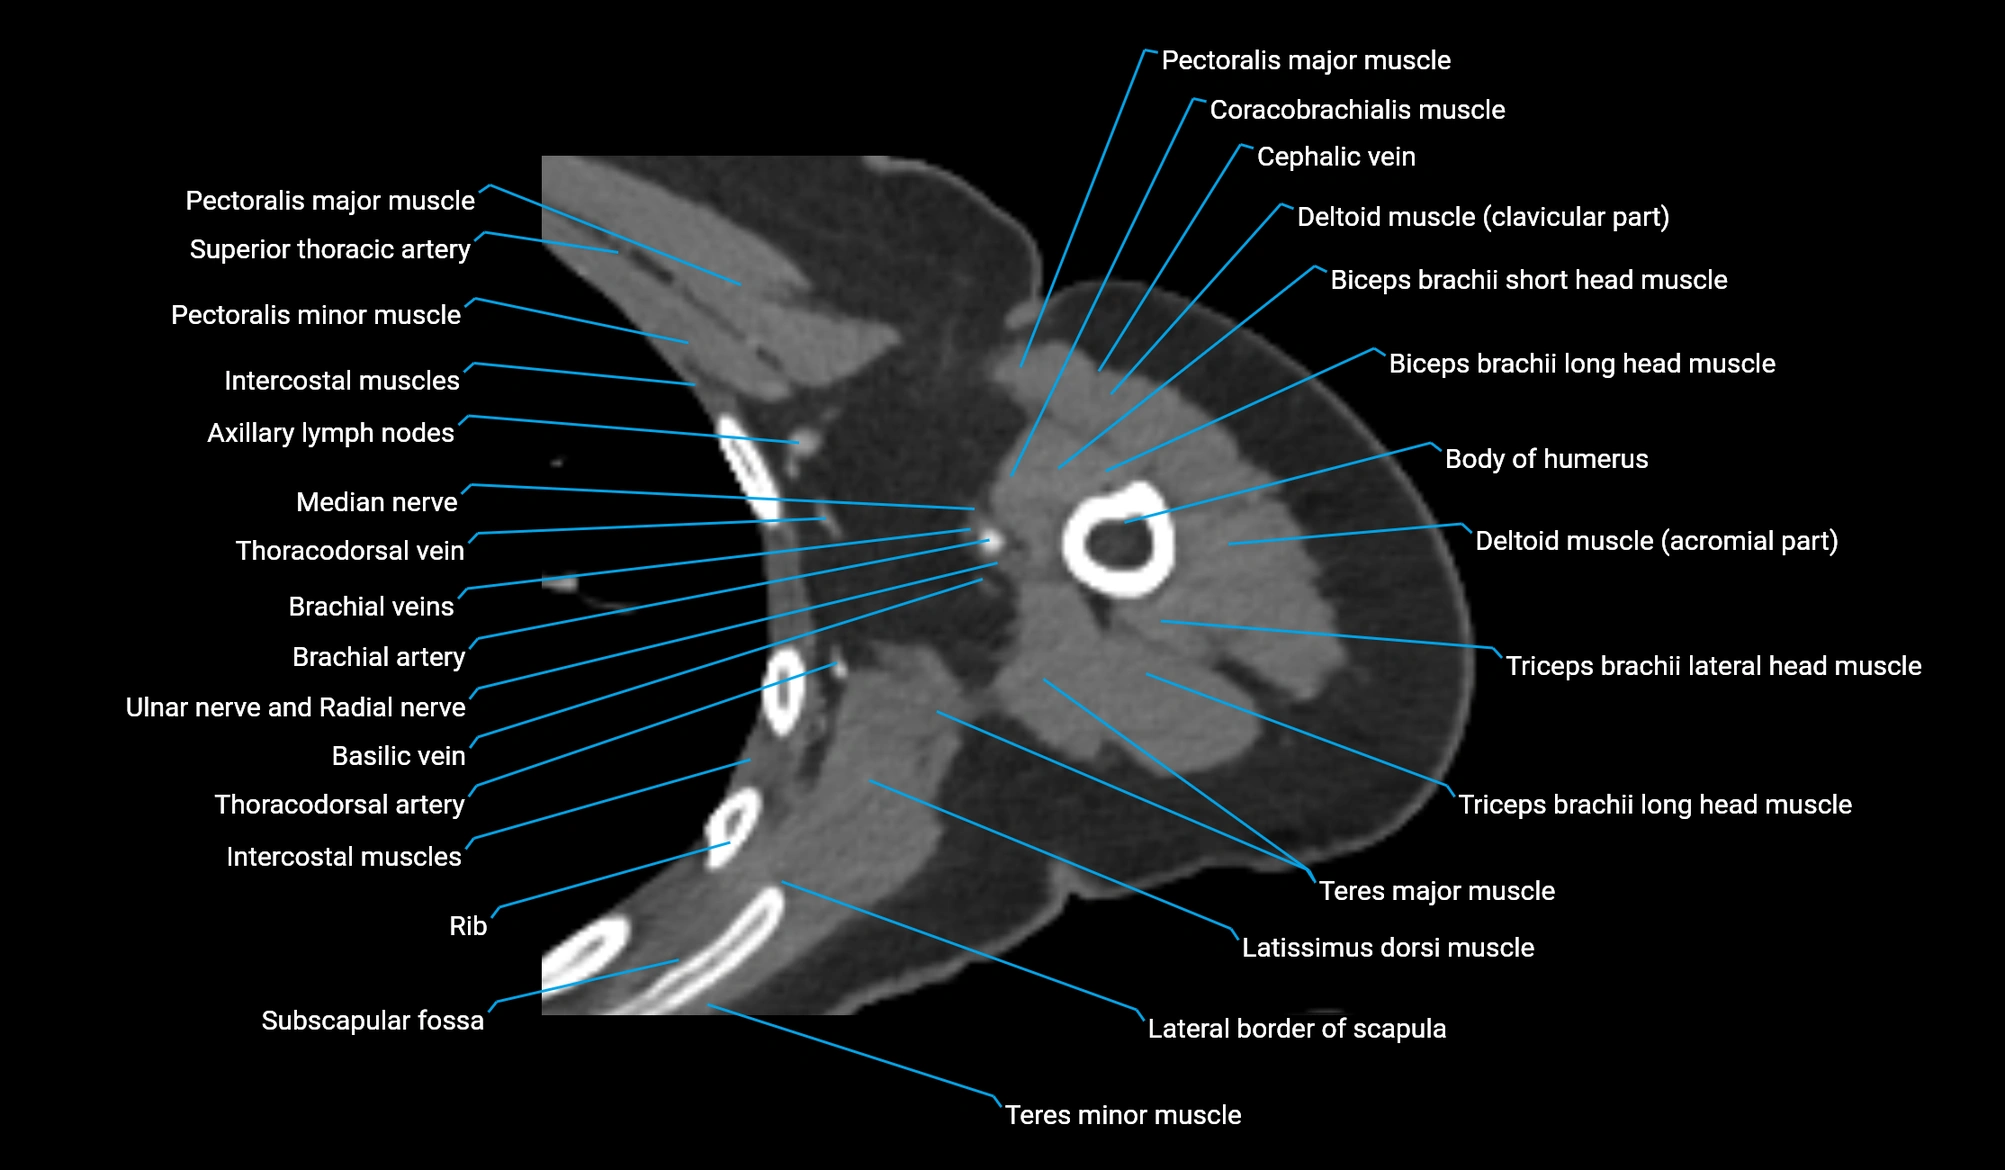

- Axillary lymph nodes

- Basilic vein

- Brachial artery

- Brachial plexus

- Brachialis muscle

- Coracobrachialis muscle

- Long head of triceps brachii muscle

- Median nerve

- Pectoralis major muscle

- Pectoralis minor muscle

- Teres major muscle

- Teres minor muscle

- Thoracodorsal artery